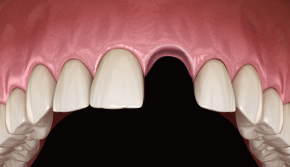

1. 술전

-

2. 터널 점막 거상